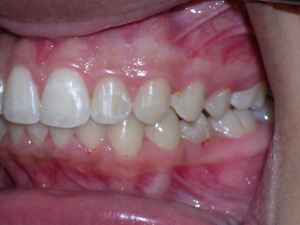

In this case, a young woman came to us with a desire to straighten her teeth. We elected to do Invisalign treatment with some enamel reduction and some dental arch expansion. Take a look...

Here she is on the day of appliance removal. You can see how the crossbite on the right has improved, as well as the lower front teeth crowding. Note that we elected to leave the lower second premolar in it’s rotated form.